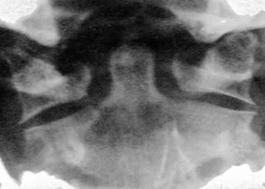

Fractura

Jefferson

Fractura Jefferson Fragmente

osoase la stanga apofizei odontoide

Fractura Jefferson Fractura spanzuratului